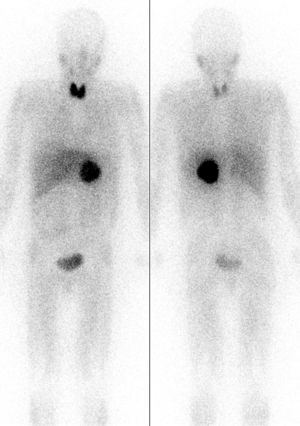

يمكن أن يساعد التصوير المقطعي المُحَوْسب أو التصوير بالرنين المغناطيسي T2 على الرأس والرقبة، والصدر، والبطن في تحديد مكان الورم. ويمكن أيضًا تحديد المكان عن طريق المسح الضوئي MIBG، باستخدام metaiodobenzylguanidine . أما التحديد الأدق فيمكن الحصول عليه في بعض مراكز المسح باستخدام PET-CT أو PET-MRI مع 18F] fluorodopamine] أو FDOPA.[10]